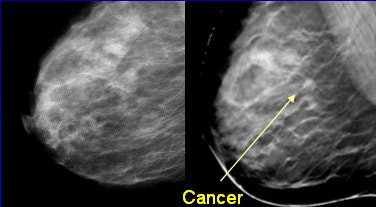

| DBT review workflow. Above, conventional mammographic prior images were automatically retrieved from PACS with CC and MLO views obtained as needed. Below, DBT MLO slice sets (35-85 slices spaced 1 mm apart) with 1800 x 2304 pixel in-plane presentation. |